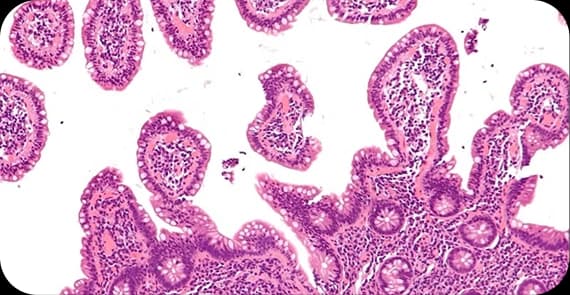

Lymph node biopsy

Lymphoma cancer diagnosis involves clinical evaluation and tissue confirmation.

A precise diagnosis allows for subtype identification and personalised lymphoma cancer treatment plans.